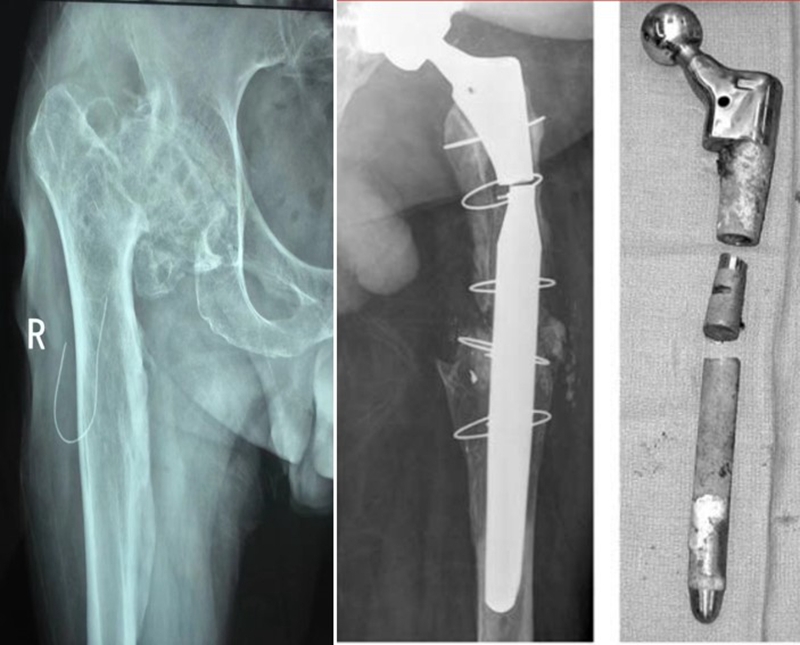

3、术中处理

②内固定的取出:良好术野,齐全工具。

③近端的重建:纠正性截骨,短缩截骨。

纠正性截骨的要求是:

①在畸形最严重的部位纠正对线不良;

②最大限度保留骨质;

③截骨部位牢固固定;

④使用长柄假体跨越截骨端。

股骨截骨的不同方法:

股骨近端截骨重建——截骨方式:横形、斜形、阶梯式及双V形截骨

优点:不改变股骨近端的解剖,保持臀中肌附丽点完整,截骨后能矫正股骨的前倾角,是较为理想的股骨缩短方法。

缺点:①骨折——截骨两端捆钢丝;②截骨端不稳定,术后骨折不愈合——足够长的远端固定型非骨水泥型假体或组配型假体,假体长度足够,避免型号过小,必要时使用骨板加强固定;③失血多、时间长。